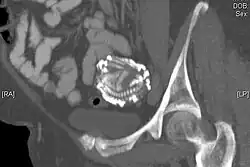

An 80-year-old woman presented in the outpatient department with severe abdominal pain. Ultrasound examination revealed a large echogenic mass (20 × 20 cm) in the right upper quadrant. An abdominal X-ray demonstrated the skeleton of a fully developed extrauterine fetus. It is presumed from the patient's history that this fetus was present for at least 40 years. Radiography revealed a fetus shrouded in a mantle of calcification. The fetus was hyper-flexed with other signs of "intrauterine" death. Fetal dentition charts dated the fetus at 34 weeks, the epiphyses being obscured by extensive calcification. In addition to subcutaneous calcification there was extensive visceral and intracranial calcification.[24] |